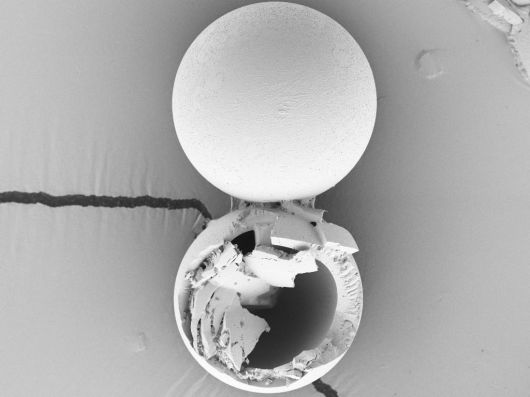

백신이 담긴 마이크로캡슐의 구조를 보여주는 주사전자현미경(SEM) 이미지./Romain Guyon1 |

연구진은 한 번의 접종으로 추가 면역 효과까지 낼 수 있는 백신 플랫폼을 개발했다. 핵심 기술은 생분해성 고분자 물질인 PLGA로 만든 마이크로 캡슐에 백신을 담는 것이다. 백신을 접종할 때 마이크로 캡슐을 함께 주입하면 1차로 주사한 백신이 면역반응을 유발하고, 정해진 시간이 지나면 캡슐이 백신을 추가로 방출해 2차 접종 효과를 낸다.

새로운 백신 플랫폼은 냉장 보관에도 적합하다. 연구진은 섭씨 4도에서 4~7주 동안 냉장 보관하고 효과를 측정했다. 그 결과 면역 효과가 냉장 보관 이후에도 유지되는 것으로 나타났다. 마이크로 캡슐은 직경이 65㎛(마이크로미터·1㎛은 100만 분의 1m)로 일반 주사 바늘로도 주입할 수 있다.